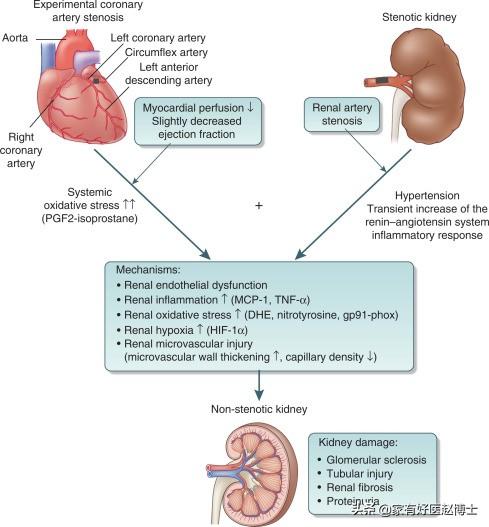

La relation entre l'hypertension et les reins est à la fois étroite et complexe, et les dommages causés aux reins par l'hypertension comprennent principalement : ① la néphrosclérose : au début de l'évolution des patients atteints d'hypertension essentielle légère et modérée, pendant une période assez longue, il n'y a pas de changements structurels et fonctionnels évidents au niveau des reins, seulement le spasme des petites artères rénales et l'affaiblissement de la fonction d'autorégulation rénale, comme la réduction de la capacité d'adaptation à des états non physiologiques tels qu'une charge élevée en sodium et une expansion volumique aiguë. Après un certain temps, en raison du spasme continu des petites artères rénales, celles-ci subissent une dégénérescence, un durcissement et un rétrécissement, et les unités rénales subissent une atrophie et une sclérose dues à l'ischémie, ce qui nuit gravement à la fonction rénale. L'hypertension primaire se manifeste d'abord par des lésions des tubules rénaux et des changements fonctionnels, le patient se manifeste par une nycturie accrue, les tests de laboratoire révèlent une petite quantité de protéines dans l'urine, principalement des protéines à petites molécules (la β2 microglobuline est un trait caractéristique), la gravité spécifique de l'urine est réduite et la capacité d'acidification de l'urine est diminuée. En général, l'hypertension primaire continue à se développer régulièrement et une petite artériosclérose rénale légère à modérée peut apparaître après 5 à 10 ans. ② athérosclérose de l'artère rénale : l'hypertension est un facteur causal important de l'athérosclérose, et l'artère rénale est un site privilégié de l'athérosclérose. L'artériosclérose rénale réduit le flux sanguin rénal, active le système rénine-angiotensine-aldostérone, provoquant une vasoconstriction, une rétention de sodium et une nouvelle élévation de la pression artérielle, formant ainsi un cercle vicieux. Environ 7 % des patients atteints d'hypertension primaire présentent une augmentation soudaine et progressive de la pression artérielle au cours de la maladie, qui se transforme en hypertension maligne. Lorsque la pression artérielle évolue vers une hypertension aiguë, une nécrose fibrinoïde des petites artères rénales se produit, et les reins sont gravement ischémiés, avec une détérioration rapide de la fonction rénale et une progression rapide vers l'urémie.

Parmi les adultes de plus de 18 ans en Chine, au moins une personne sur quatre souffre d'hypertension artérielle, et l'incidence de l'hypertension artérielle continue d'augmenter. Le rein est un organe étroitement lié au développement de l'hypertension. Nous savons tous que le rein est responsable de la régulation de l'équilibre eau-sel dans l'organisme (équilibre liquide-électrolyte), l'augmentation de l'eau et du sel dans l'organisme entraîne facilement une augmentation de la pression artérielle ; et l'augmentation de la pression artérielle affecte l'hémodynamique des reins, entraînant des lésions rénales. C'est pourquoiLes reins sont à la fois l'organe régulateur de la pression artérielle et l'organe cible des lésions dues à l'hypertension, et il existe un cercle vicieux entre l'hypertension et les lésions rénales.。

L'hypertension à long terme, si elle n'est pas contrôlée, peut conduire à l'athérosclérose des petites artères rénales, à l'hypoplasie rénale, à l'hypoplasie rénale, à une nouvelle augmentation de la pression artérielle, ce qui entraîne un cercle vicieux, et finalement, la fonction rénale continue à se détériorer, devenant une urémie.

2) Quel est l'effet de l'hypertension artérielle sur les reins ?

Un choc prolongé d'hypertension artérielle entraîne, dès le début, une modification de la membrane filtrante mentionnée plus haut, c'est-à-dire une modification de la perméabilité, de sorte que certaines des plus grosses molécules, telles que l'albumine, qui ne pourraient autrement pas traverser la membrane filtrante, s'échappent de la membrane filtrante et que l'albumine puisse être détectée dans l'urine. Une pression artérielle plus élevée, pendant une période plus longue, agit sur les artères des reins, provoquant le rétrécissement de certaines des petites artères des reins, ce qui finit par réduire la quantité de sang qui atteint la membrane filtrante et, naturellement, la quantité d'urine produite sera également réduite, d'où une diminution de la quantité d'urine.